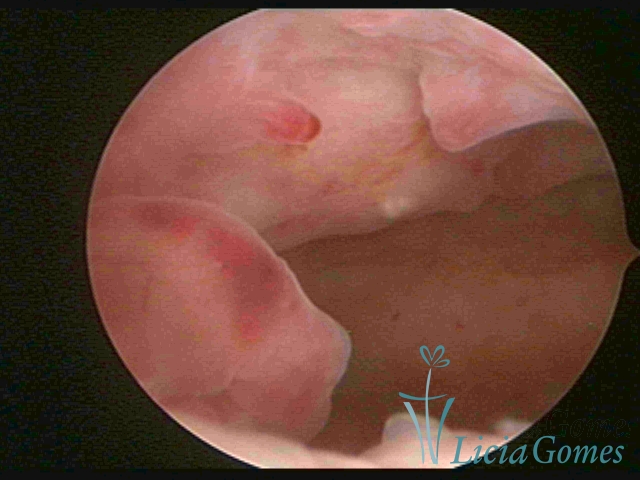

Podem ocorrer em uma região da cavidade uterina, considerada hipertrofia focal ou ocupando toda a sua extensão, então denominada hipertrofia difusa.

A hipertrofia polipoide é visualizada quando o crescimento endometrial é mais pronunciado, e como o espaço da cavidade uterina é limitado, forma dobras ou sulcos, simulando lesões pseudo polipoides ou polipoides.